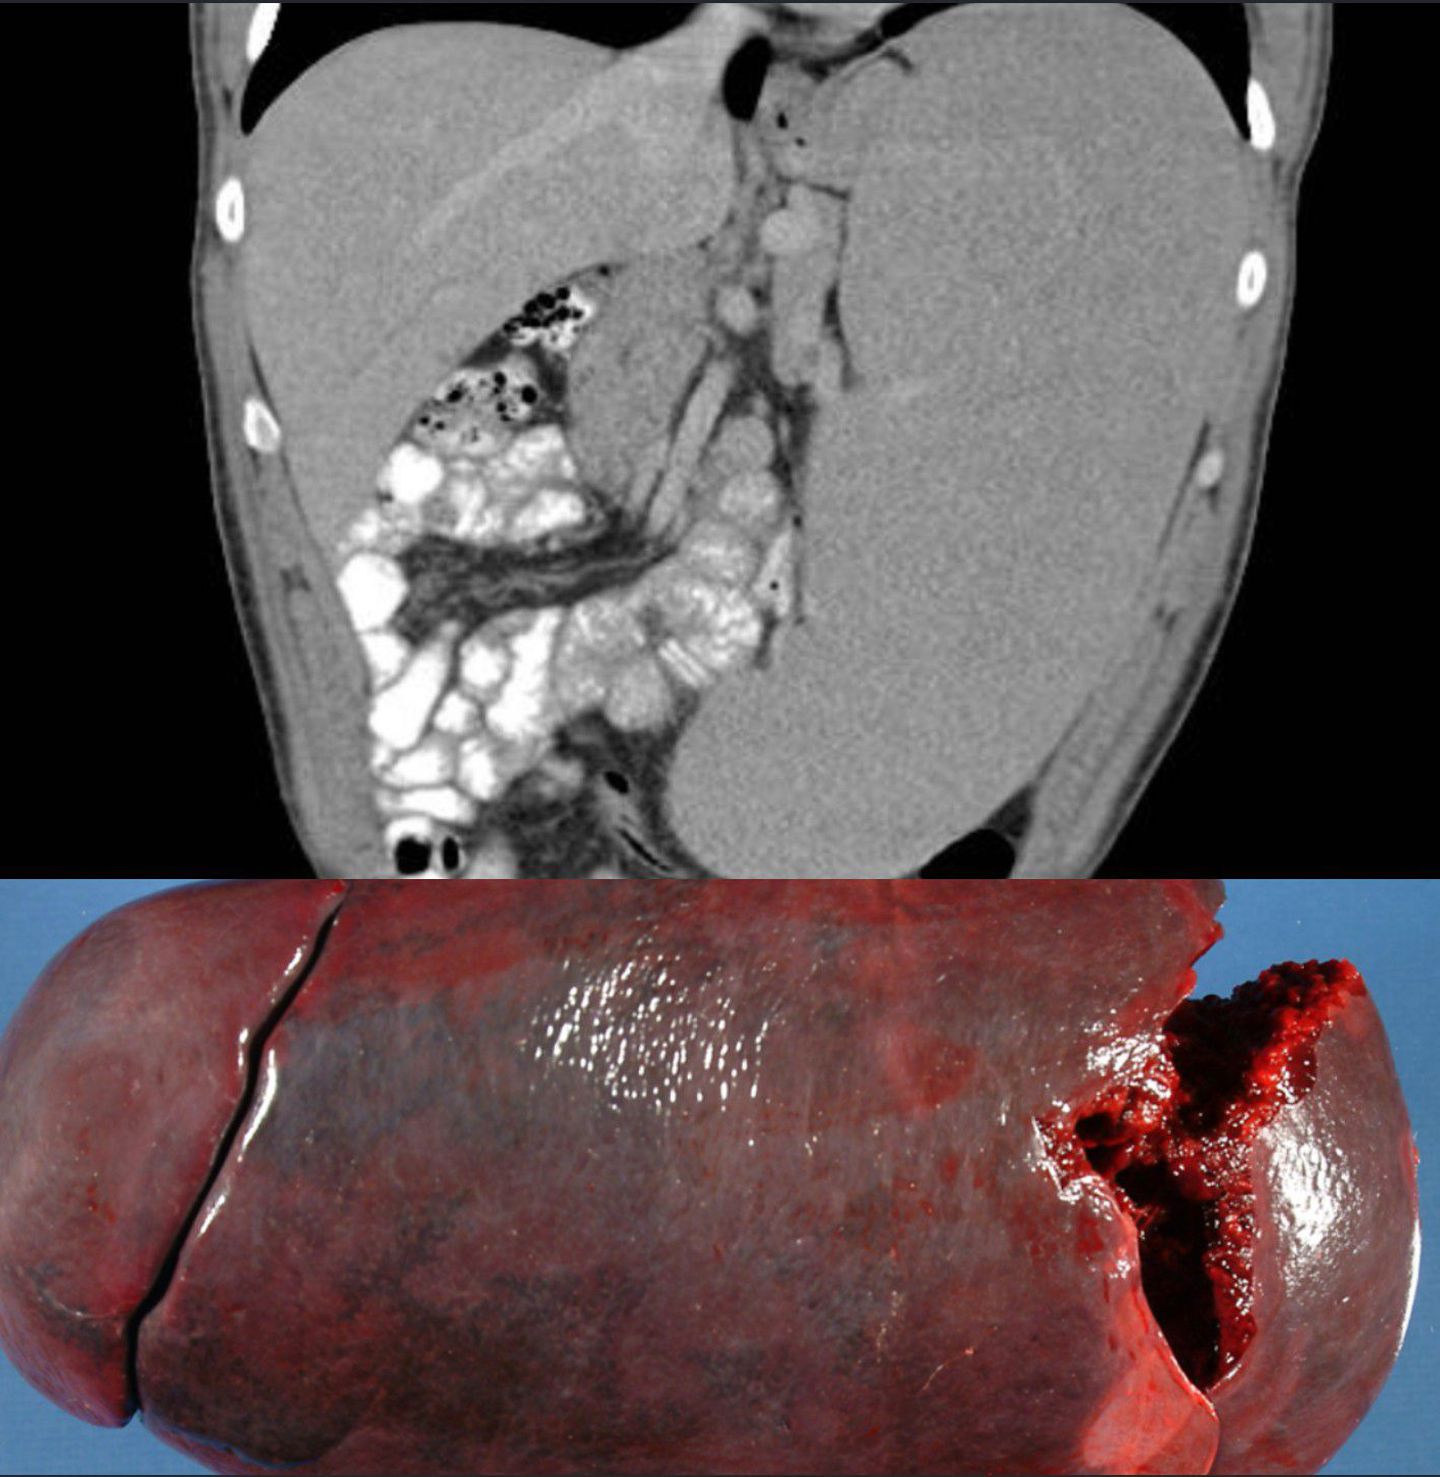

Splenomegaly is a magnification of the spleen. The spleen generally stays in the left upper quadrant (LUQ) of abdomen of human being. It is a one cardinal sign of the four cardinal signs of hypersplenism which is some decreasing in the number of circulating blood cells disturbing erythrocytes , granulocytes, or platelets in any combination. A compensatory proliferative reaction happens in the bone marrow as well as the potential for improvement of these abnormalities by the splenectomy. Splenomegaly is generally related with enhanced workload suggesting that it is a reaction to hyper function. So it is not surprising that it is connected with any disease procedure involving abnormal red blood cells being damaged in the spleen.